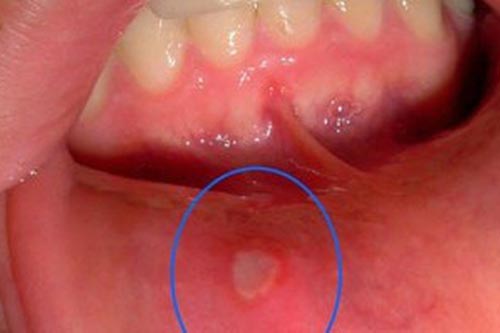

DNVN - Nhiệt miệng là bệnh viêm loét khoang miệng rất thường gặp. Hiện nay, nhiều người có xu hướng lựa chọn giải pháp từ thiên nhiên chứa kháng sinh thực vật, kháng viêm thực vật, giúp tăng sức đề kháng tế bào khoang miệng, điển hình là gel làm sạch miệng và kháng khuẩn Gumimouth.

Nhiệt miệng gây đau và khó chịu, tuy nhiên không cần dùng đến những loại thuốc đắt tiền, bạn hoàn toàn có thể tự chữa nhiệt miệng tại nhà bằng mẹo dưới đây.

Nhiệt miệng gây cảm giác khó chịu khi nói chuyện, ăn uống. Nó ảnh hưởng đến sinh hoạt hàng ngày của bạn. Dưới đây là một số cách chữa nhiệt miệng rất có ích cho bạn.